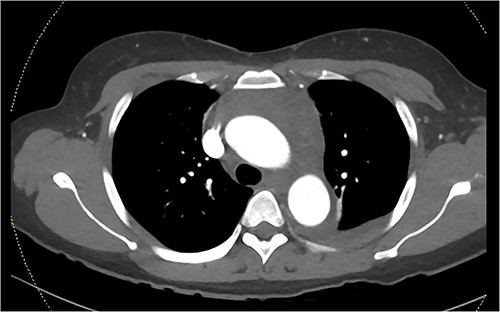

A computed tomography pulmonary angiogram (CTPA) was performed in the Emergency Department. Marked cresenteric aortic thickening from the level of the origin of the brachiocephalic trunk to the aortic hiatus in the diaphragm was noted, seen in Fig. 1. The CTPA was subsequently reported as an acute aortic intramural haematoma. The patient was transferred to the intensive care unit for blood pressure control with intravenous labetalol and cardiac monitoring.